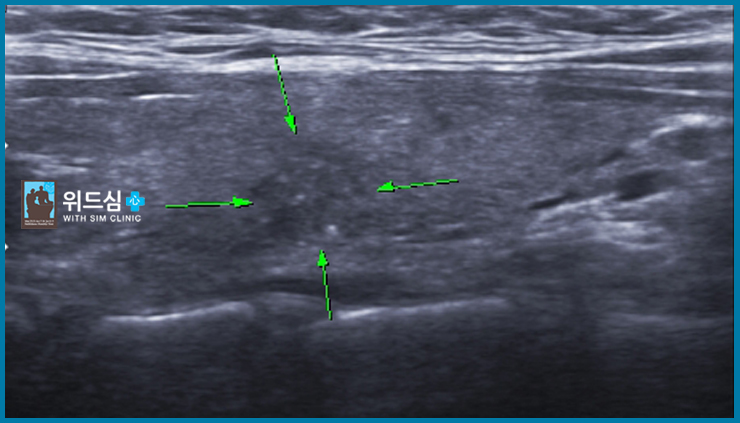

갑상선 미세 석회화 초음파 약 1cm 크기의 경계가 불분명한 미세 석회화를 동반한 저음영 병변

경부 임파선 비대 경부 임파선 전이로 생각되는 경부 임파선 비대